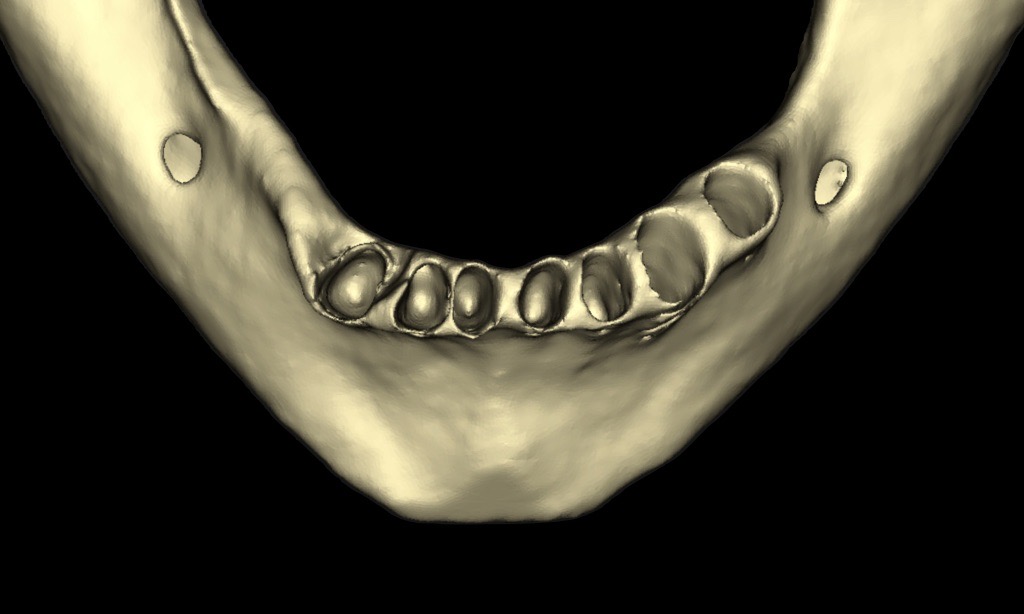

A CBCT scan was taken to determine the quality and quantity of the bone in the edentulous areas. The radiographic analysis showed adequate bone height in the areas of tooth extraction, allowing for immediate implant placement. The remaining bone provided sufficient support for initial stability during implant placement. Sufficient horizontal ridge width was observed in the potential implant sites, ensuring proper implant positioning without the need for additional ridge augmentation. Bone quality was favourable for immediate implant placement. The anterior maxilla presented moderate to good bone density (Type II–III) and the mandible excellent bone density (Type I–II), particularly in the posterior regions, indicating high primary stability for implants. Subsequently, digital impressions were obtained using the TRIOS intra-oral scanner (3Shape) and exported in STL file format (Figs. 8 & 9).

After a healing period of five months and successful osseointegration, the process for the definitive restorations was initiated. The chosen material was milled monolithic zirconia, and Variobase final abutments was used, placed on the screw-retained abutments to ensure excellent stability and retention of the definitive restorations (Figs. 69–75).

Figs. 69–75: The definitive restorations were fabricated after a five-month healing period